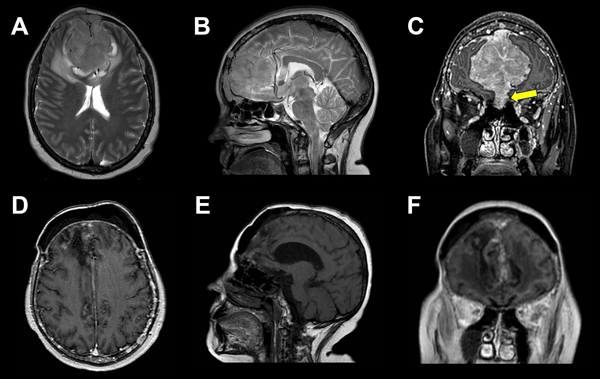

En el estudio de resonancia magnética (RM) de encéfalo se observó lesión extraaxial expansiva bifrontal con compromiso del seno frontal y tercio anterior de seno sagital superior de aspecto sólido e hipervascularizada, de aproximadamente 5.2 x 5.8 x 7.7 cm. Lesión isointensa en secuencia T1 e hipo-hiper intensa en secuencia T2, que realzaba de manera homogénea a la administración de contraste paramagnético con engrosamiento leptomeníngeo asociado. En secuencia FLAIR, se evidenció edema perilesional con colapso de las astas ventriculares frontales. En AngioRM se advirtió un gran aporte vascular de ambas arterias cerebrales anteriores, y en ventana ósea, múltiples lesiones osteolíticas en calota craneana (Figura 2).

Figura 2. A, B, C) RM preoperatoria. A) Corte axial en secuencia T2, lesión isointensa con marcado edema perilesional. B) Corte sagital en secuencia T2, arterias pericallosas desplazadas. C) Corte coronal en secuencia T1, lesión extraaxial con realce homogéneo a la administración de contraste. Invasión de los senos etmoidales (flecha amarilla). D, E, F) RM postoperatoria, en corte axial sagital y coronal se evidencia lodge de resección de LOE bifrontal sin remanente lesional y huella de craneoplastia.

Se han descripto dos patrones de extensión, la diseminación hematógena de células plasmáticas y la diseminación continua directa desde lesiones líticas erosionadas del cráneo.1,12 En cuanto al diagnóstico diferencial, destacan las similitudes imagenológicas con los meningiomas, tumores que surgen de las células aracnoideas de la duramadre y constituyen una de las neoplasias intracraneales más comunes. En RM suelen verse como una masa extraaxial redondeada de bordes suaves y circunscrita con base ancha en la superficie dural, presentan hipointensidad en secuencia T1 e hiperintensidad en secuencia T2 con realce homogéneo a la administración de contraste y el signo de “cola dural” que no es patognomónico de esta entidad y puede advertirse en otras lesiones como hemangiopericitoma, metástasis o linfomas; esto hace casi indistinguible la diferenciación preoperatoria en casos como este (ver Figuras 1 y 2).